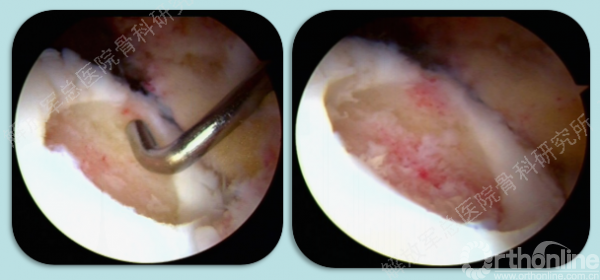

损伤软骨组织的清理(术中备了眼科器械,来辅助完成)。

损伤软骨组织的清理。